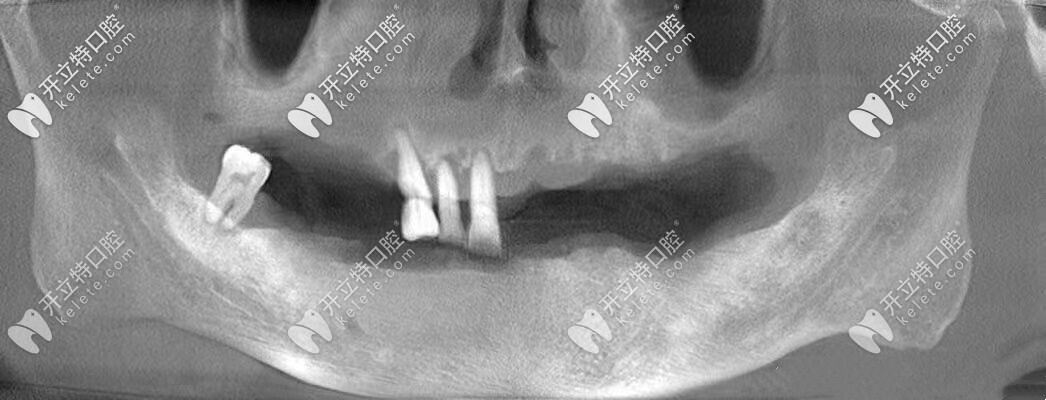

張叔牙齒的上頜僅剩3顆牙,下頜僅剩1顆牙,他之前一直戴的是活動(dòng)假牙,但是當(dāng)看著支持掛鉤的基牙一顆顆松動(dòng)、齲壞到拔除,張叔的心里也是很難過(guò)的。